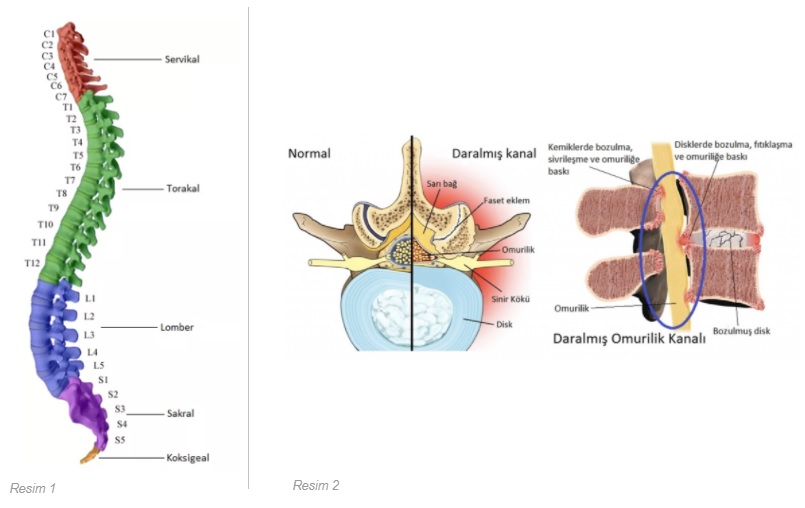

Omurilik, omur gövdelerinin arkasındaki kanalda bulunan bir yapıdır. Başın hemen alt kısmından başlayarak aşağıya uzanır. Omurgada boyun (servikal), göğüs (torakal), bel (lomber), sakral ve koksigeal bölge olmak üzere 5 ayrı omur grubu vardır (Resim 1). Omurilik kanalı daralması daha çok bel ve boyun bölgesinde görülür. Bel bölgesinde 5 adet omur vardır. Bu bölge beden ağırlığının en çok yoğunlaştığı omurga bölgesidir. Burada yer alan diğer oluşumlar; omurlar arasında bulunan disk (bel fıtığı bu yapıdan oluşur), omurların birbirleriyle eklem yaptığı faset eklemler, omurların gövdesinin arkasından geçen kuvvetli bağ dokusu ve omurilik kesesi arkasında yer alan sarı bağdır.

Omurilik kanalı daralması, omurların hemen arkasında yer alan omurilik kanalının çepeçevre daralarak, yukardan aşağı içinden geçen omuriliği çeşitli seviyelerde sıkıştırması ve beraberinde de sinir köklerine yaptığı basıya denir. Bel omurilik kanalı daralması dejeneratif bir süreçtir. Bu sürece yukarıda sayılan tüm yapıların dejeneratif değişimleri katkıda bulunur ve hasta bir süre sonra dar kanal sorunu ile karşı karşıya kalabilir. Omurlar arası disklerin yaşlandıkça su içeriğinin azalması, faset eklemlerin içe doğru büyümeleri, omurlar arkası bağın kalsifiye olarak (kireçlenerek) omuriliği önden, omurilik arkasında yer alan sarı bağın kalınlaşarak arkadan bası yaratması bel omurilik kanalı daralmasında ana etkenlerdir (Resim 2).